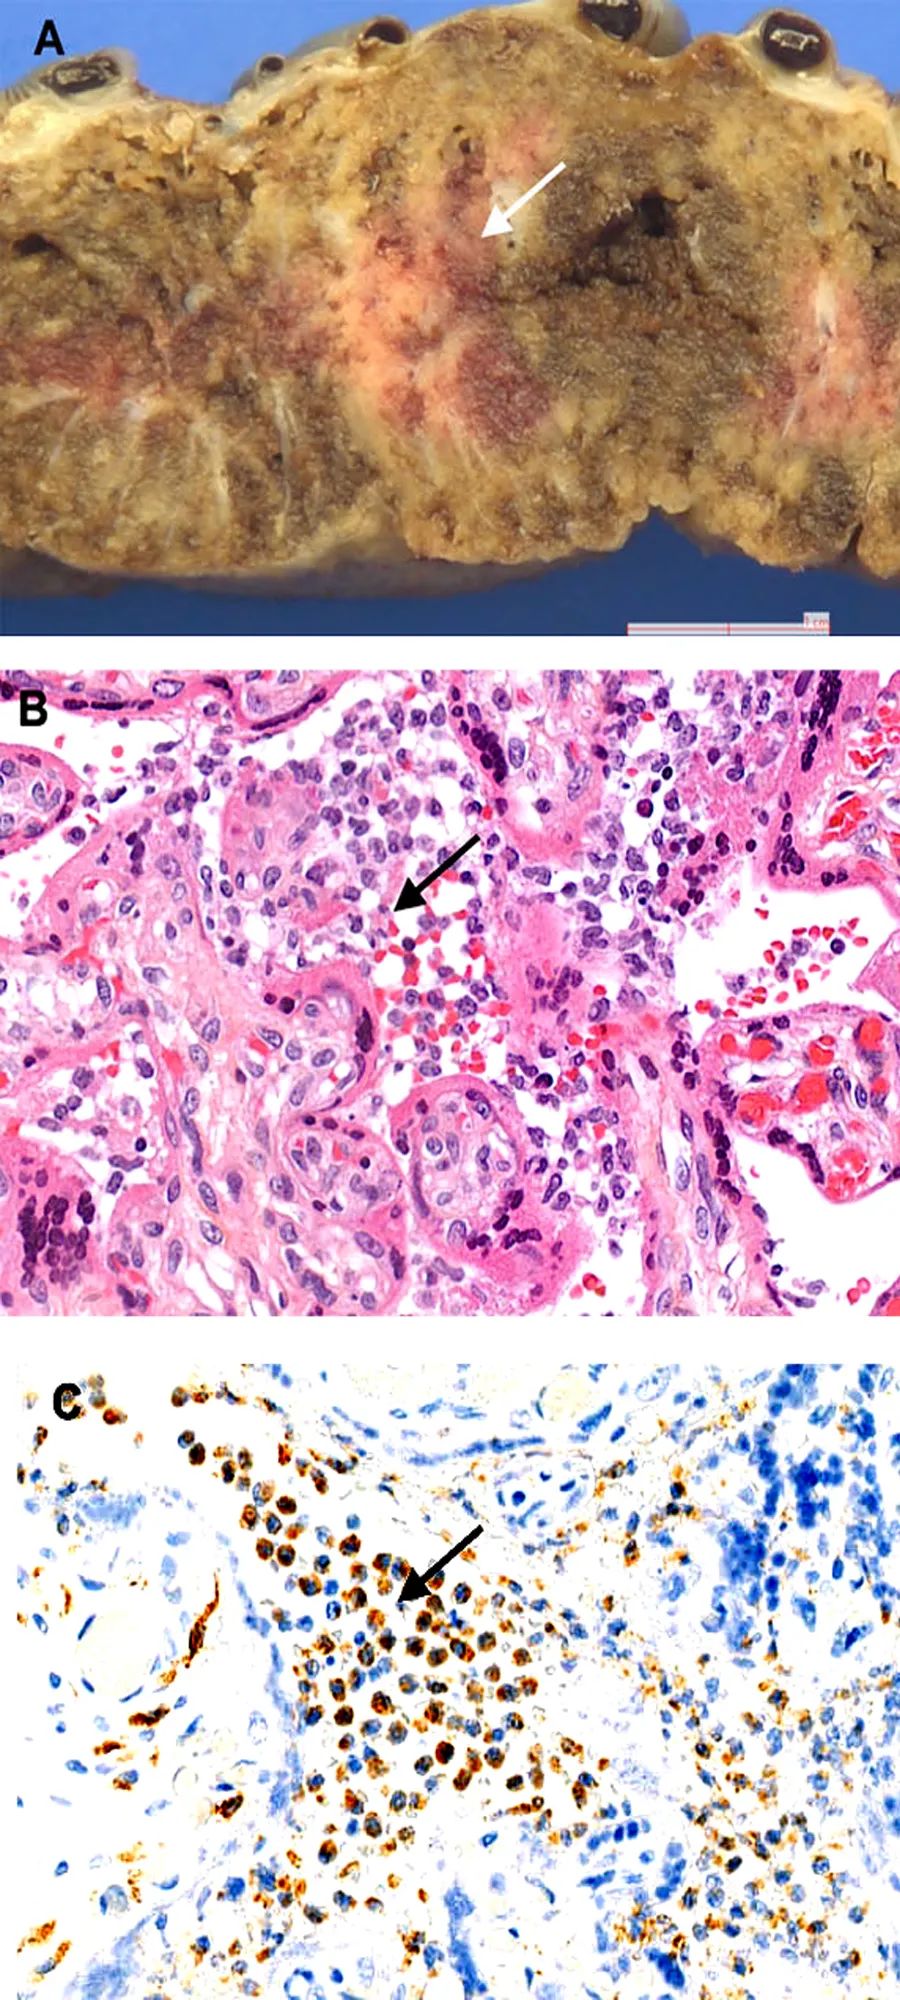

胎盘策划病理学检查显示弥漫性绒毛周围纤维蛋白沉积,伴有梗死和急性和慢性绒毛间质增生。下图显示了胎盘大体和显微镜检查以及免疫策划化学的结果。

用抗SARS-CoV-2n蛋白抗体进行免疫染色,可见绒毛周围滋养层细胞胞浆呈强阳性。特殊染色及免疫组化均未发现其他致病菌。